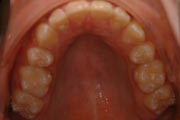

Crowding

After